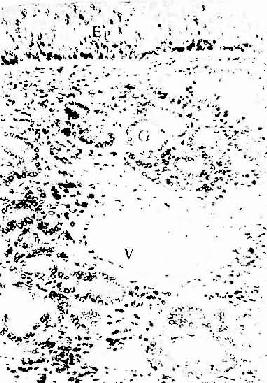

呼吸部(respiratory region)的面积较大,占鼻粘膜的大部,包括下鼻甲中鼻甲鼻道鼻中隔中下份等粘膜。生活状态的粘膜呈淡红色,表面为假复层纤毛柱状上皮,杯状细胞较多(图14-1)。上皮纤毛向咽部快速摆动,将粘液及粘着的尘粒推向咽部而被咳出。固有层结缔组织内有较多粘液腺、浆液腺和混合腺,分泌物经导管排入鼻腔,与上皮内杯状细胞分泌物共同形成一层粘覆于纤毛上。呼吸部粘膜的血液供应较丰富,并有丰富的静脉丛,中、下鼻甲处尤多,使粘膜形成许多小隆起。静脉丛管壁薄,腔大似窦状,它们随动静脉吻合的开放和关闭而有周期性充血变化,通过散热和渗出,对吸入空气起加温和湿润作用,患鼻炎时,静脉丛异常充血,粘膜肿胀,分泌物增多,鼻道变窄。固有层内淋巴组织较多,还可见嗜酸性粒细胞嗜碱性粒细胞肥大细胞,患过敏性鼻炎时,鼻分泌物中可见此类细胞。

人鼻呼吸部粘膜

图14-1 人鼻呼吸部粘膜HE × 100

Ep假复层纤毛柱状上皮 G腺泡 V小静脉